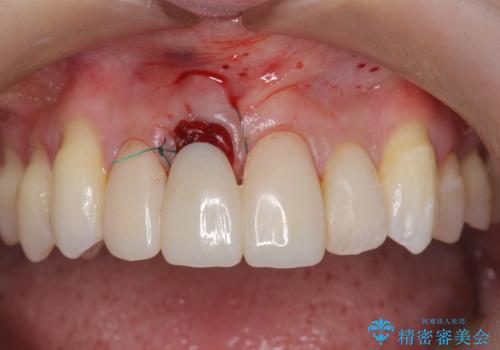

上顎4前歯は、根管治療の既往があり、虫歯も見られたことからブリッジによる治療で審美性の回復を行うとともに臨在歯の虫歯もセラミック治療を行っていきます。

- 44万円(仮歯・ジルコニアクラウン×4)費用は治療当時の料金となります

欠損部の歯ぐきの量が足りない場合は、移植を行い歯肉を増大させることもありますが、今回は仮歯で様子を見た結清掃性・審美性に問題が出なかったので行いませんでした。